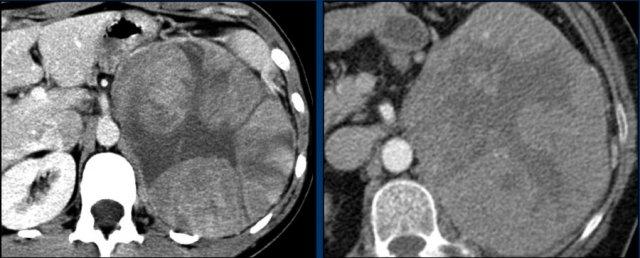

CT thì tĩnh mạch mặt cắt ngang bên trái cho thấy một tổn thương tuyến thượng thận phải kích thước lớn, ngấm thuốc không đồng nhất kèm một nang nhỏ, không thể chẩn đoán là u tuyến (adenoma) bằng CT đánh giá độ thải thuốc, do đó được xếp vào nhóm tổn thương chưa xác định.

Metanephrine tự do trong huyết tương tăng cao và tổn thương được chẩn đoán là u tủy thượng thận (pheochromocytoma).

SPECT MIBG để phân giai đoạn cho thấy sự hấp thu mạnh chỉ ở tuyến thượng thận phải.

PET-CT cũng được thực hiện, nhưng ngược lại chỉ cho thấy sự hấp thu cao hơn gan bình thường một chút.

Đây là điều rất bất thường đối với u tủy thượng thận, vốn thường có sự hấp thu FDG rất mạnh, ngay cả khi lành tính.

Nếu khối u nguyên phát thiếu sự hấp thu FDG, độ nhạy để phát hiện di căn trên PET-CT FDG sẽ rất thấp.